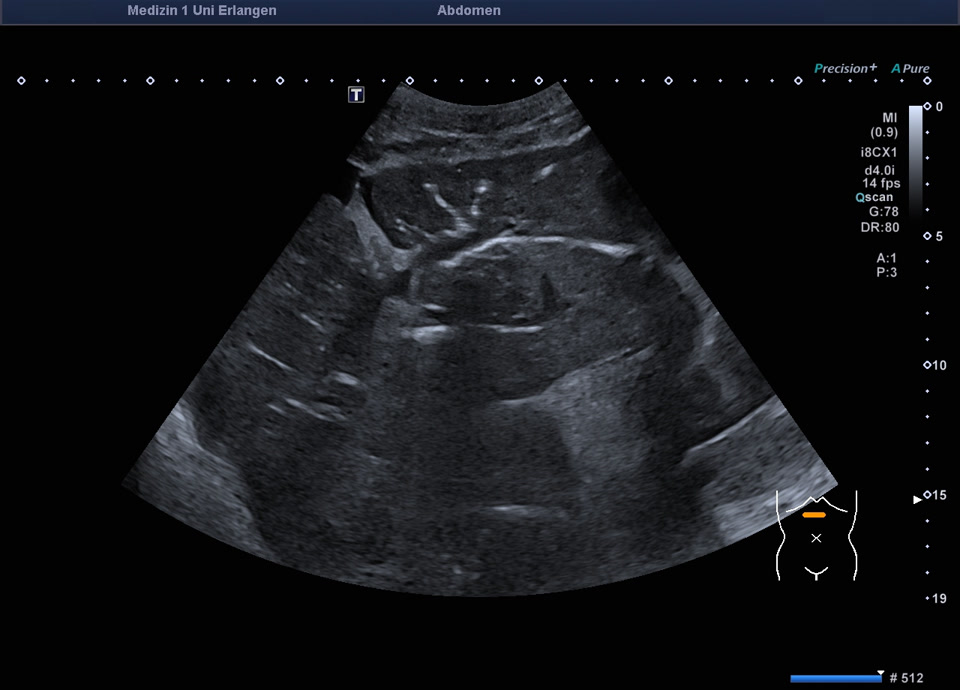

71-jähriger Patient mit Z.n. Duodenalkarzinom und Tumorresektion mit Duodeno-Jejunostomie. Circa ein Jahr nach Resektion zeigt sich im Ultraschall eine intra- und extrahepatische Cholestase mit Cholangitis. In der ERCP zeigt sich ein Tumorrezidiv mit exophytisch wachsender Tumorstruktur in der Papillenregion, die Sondierung der Papille gelingt nicht. Am Folgetag wird eine Choledochoduodenostomie mit Einbringung eines Lumen-Apposing Metal Stent (LAMS) endosonographisch durchgeführt. Hierbei entleert sich reichlich trübe Galle. Die Folgeuntersuchung nach drei Tagen zeigt eine Aerobilie (-> somit Beweis der korrekten Lage des Stents).